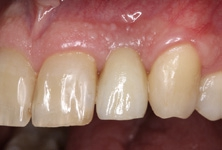

Der klinische Befund zeigte eine definitive Versorgung auf 12 und eine temporäre Versorgung auf 22. Dahingegen lag bei der Implantatversorgung in regio 22 der Verdacht auf eine partielle Fibro-Osseointegration vor (Abb. 1 und 2) [9,10].

Nach einer Ästhetikeinprobe wurde die Zirkoniumdioxidkrone mit Multilink Hybrid Abutment Zement (Ivoclar Vivadent) auf dem PEKK-Abutment verklebt (Abb. 25–28). Die Klebeüberschüsse wurden entfernt, die subgingivalen Anteile sorgfältig poliert und gereinigt. Die Abbildung 29 zeigt das individuell ausgeformte Weichgewebsprofil vor der definitiven Insertion der Hybridabutmentkrone, die mithilfe einer neuen Titanabutmentschraube eingesetzt wurde. Nach dem Einsetzen der Versorgung mit 25 Ncm wurde eine Röntgenkontrollaufnahme angefertigt. Da das Hochleistungspolymer nicht röntgenopak ist, bedarf es etwas Erfahrung bei der Passungskontrolle. Die Aufnahme sollte im rechten Winkel zur Plattform auftreffen, um dann eine parallel verlaufende dunkle Scheibe in einer Höhe von 0,55 mm über dem Implantat zu erkennen (Abb. 30 und 31). Mithilfe von Zusätzen, wie z. B. Bariumsulfat, könnte der Hochleistungskunststoff röntgenopak gefertigt werden. Allerdings würden diese das Material schwächen, wodurch die herausragenden Eigenschaften von PEKK, wie Stabilität, Duktilität und Abdichtung, minimiert würden. Beim Followup nach zwölf Monaten zeigten sich eine stabile Weichgewebesituation und geschlossene Interdentalräume (Abb. 32).